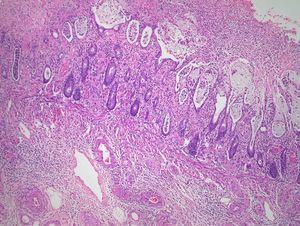

A los 15 días del ingreso el paciente presentó inestabilidad hemodinámica, caída del hematocrito y hematoquecia abundante, precisando una laparotomía urgente con resección de sigma y recto hasta un tercio inferior (tipo Hartman) y colostomía de descarga en fosa ilíaca derecha. El estudio macroscópico describía una pieza de 45 cm de longitud con 11 cm de perímetro proximal y 8 cm de perímetro distal, con moderada estenosis intraluminal, mucosa ampliamente ulcerada y cubierta en zonas por material hemorrágico. El estudio anatomopatológico (figura 3 y figura 4) reveló extensa necrosis de la mucosa colónica que se encontraba cubierta por un material fibrino-leucocitario junto con hiperplasia miointimal en venas de diferente tamaño. En las venas mesentéricas de mayor tamaño destacaba la presencia de trombos organizados y recanalizados, en los que se evidenciaban depósitos de hemosiderina con la tinción de Perls. El meso presentaba edema y múltiples focos de necrosis en la grasa pericolónica; todo ello, sugestivo de EVOIM como primer diagnóstico etiológico. Dada la buena evolución posoperatoria, el paciente fue dado de alta hospitalaria para continuar controles ambulatorios.

Figura 3. Anatomía patológica.

Figura 4. Anatomía patológica.